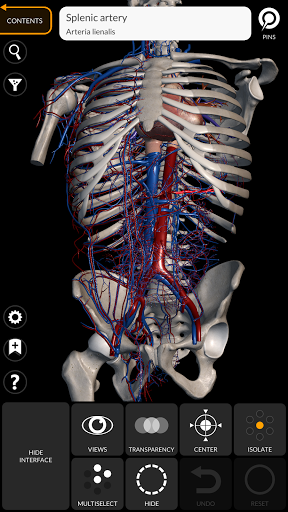

"Anatomy 3D Atlas" vous permet d'étudier l'anatomie humaine de manière simple et interactive.

Grâce à une interface simple et intuitive, il est possible d'observer chaque structure anatomique sous n'importe quel angle.

Les modèles anatomiques 3D sont particulièrement détaillés et avec des textures jusqu'à une résolution de 4k.

La subdivision par régions et les vues prédéfinies facilitent l'observation et l'étude de parties individuelles ou de groupes de systèmes et les relations entre différents organes.

• Système cardiovasculaire

• Option pour masquer ou isoler un ou plusieurs modèles sélectionnés

• Filtrez pour masquer ou afficher chaque système

• Fonction de transparence